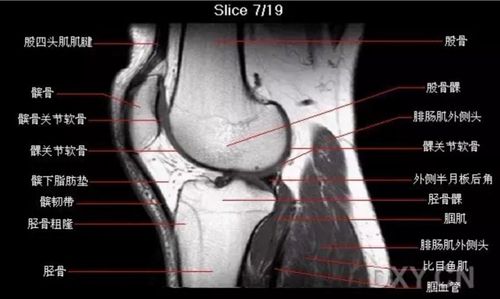

膝关节核磁共振读片

【关节影像】膝关节的磁共振(mri)解剖表现

膝盖核磁共振片子图解